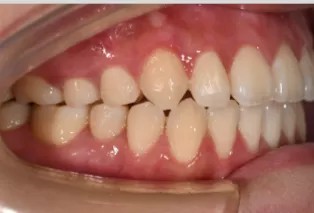

Photos intra-orales après traitement